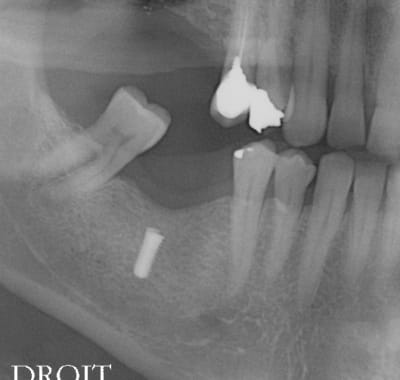

l'erreur vient dans ce cas pas du guide mais de mon inexpérience, le maillon faible ( de RENOUARD) c'est moi.

et là mauvaise nouvelle, j'ai voulu sortir l'implant , mais l'implant s'en va pour trois mois. va falloir sortrir la fraise à os, l'insert diamanté, et les loupes

je suis effectivement un petit poseur, j'ai du poser entre 150 et 200 implants, en dix ans d'implanto.

à mon avis tu augmenter fortement tes problèmes si tu attends 3 mois, l'os peut se reformer et tu ne trouveras plus ton implant.... si tu stress trop avec le patient, fais toi assister par un confrère le patient ne t'en voudra pas.

2 solutions: soit retirer l'implant soit faire une empreinte et faire faire un pilier long (titane) lisse qui va transformer ton implant en transosseux/transmuqueux... si tu n'as pas de ciment pour la jonction c'est tout à fait jouable.

soit tu t'amuse à l'enlever (le plus simple est de trouver un outil long et de dévisser, ou bien: le trépan....

perso j'irai le chercher de suite...

si nécessaire meuler l'épaulement pour insérer à nouveau le porte implant ainsi tu as les 2 possibilités ou remonter en rotation ou en traction puisque la vis le maintiendra à l'implant.

oui finalement, lambeau , j ai enlevé de l os à la fraise, puis à la fin avec un insert à boule diamantée, pour finir sans abîmer la tête de vis ( conseil que j avais lu sur eugenol). Puis j ai mis une grosse vis de cicat.

Trois semaines plus tard j ai fait mon empreinte puis mis la couronne scellée (,cvimar) sur pilier vissé

Quelques mois plus tard le patient est revenu avec la couronne qui bougeait. J ai percé la couronne pour tout démonter, mais finalement c était juste la couronne qui était descellée , je n avais pas utilisé d arrache couronne par peur d abîmer la vis. En la dent bougait mais tenait grâce aux points de contact proximaux. Le pilier était vissé et n avait pas bougé

Finalement j ai fait une nouvelle couronne transvissée.